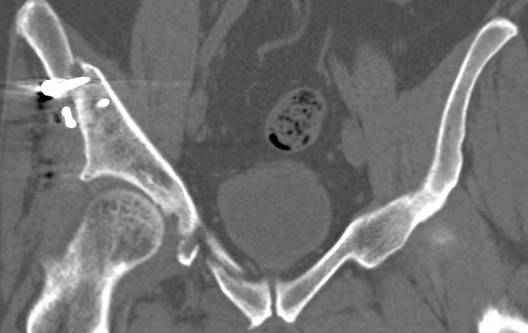

высылаю дополнительно сканы.

>Вопрос к знатокам: Так что это?

итак, второй вариант: высокий двухколонный с вовлечением КПС... Ни одно из основных повреждений не репонировано, кроме задней стенки. Скорее всего попытка реконструкции вертлуги сейчас будет очень травматичной и не очень эфективной, т.е. вероятный риск более значим, чем ожидаемая польза... Лучше подождать, и потом сразу эндопротез